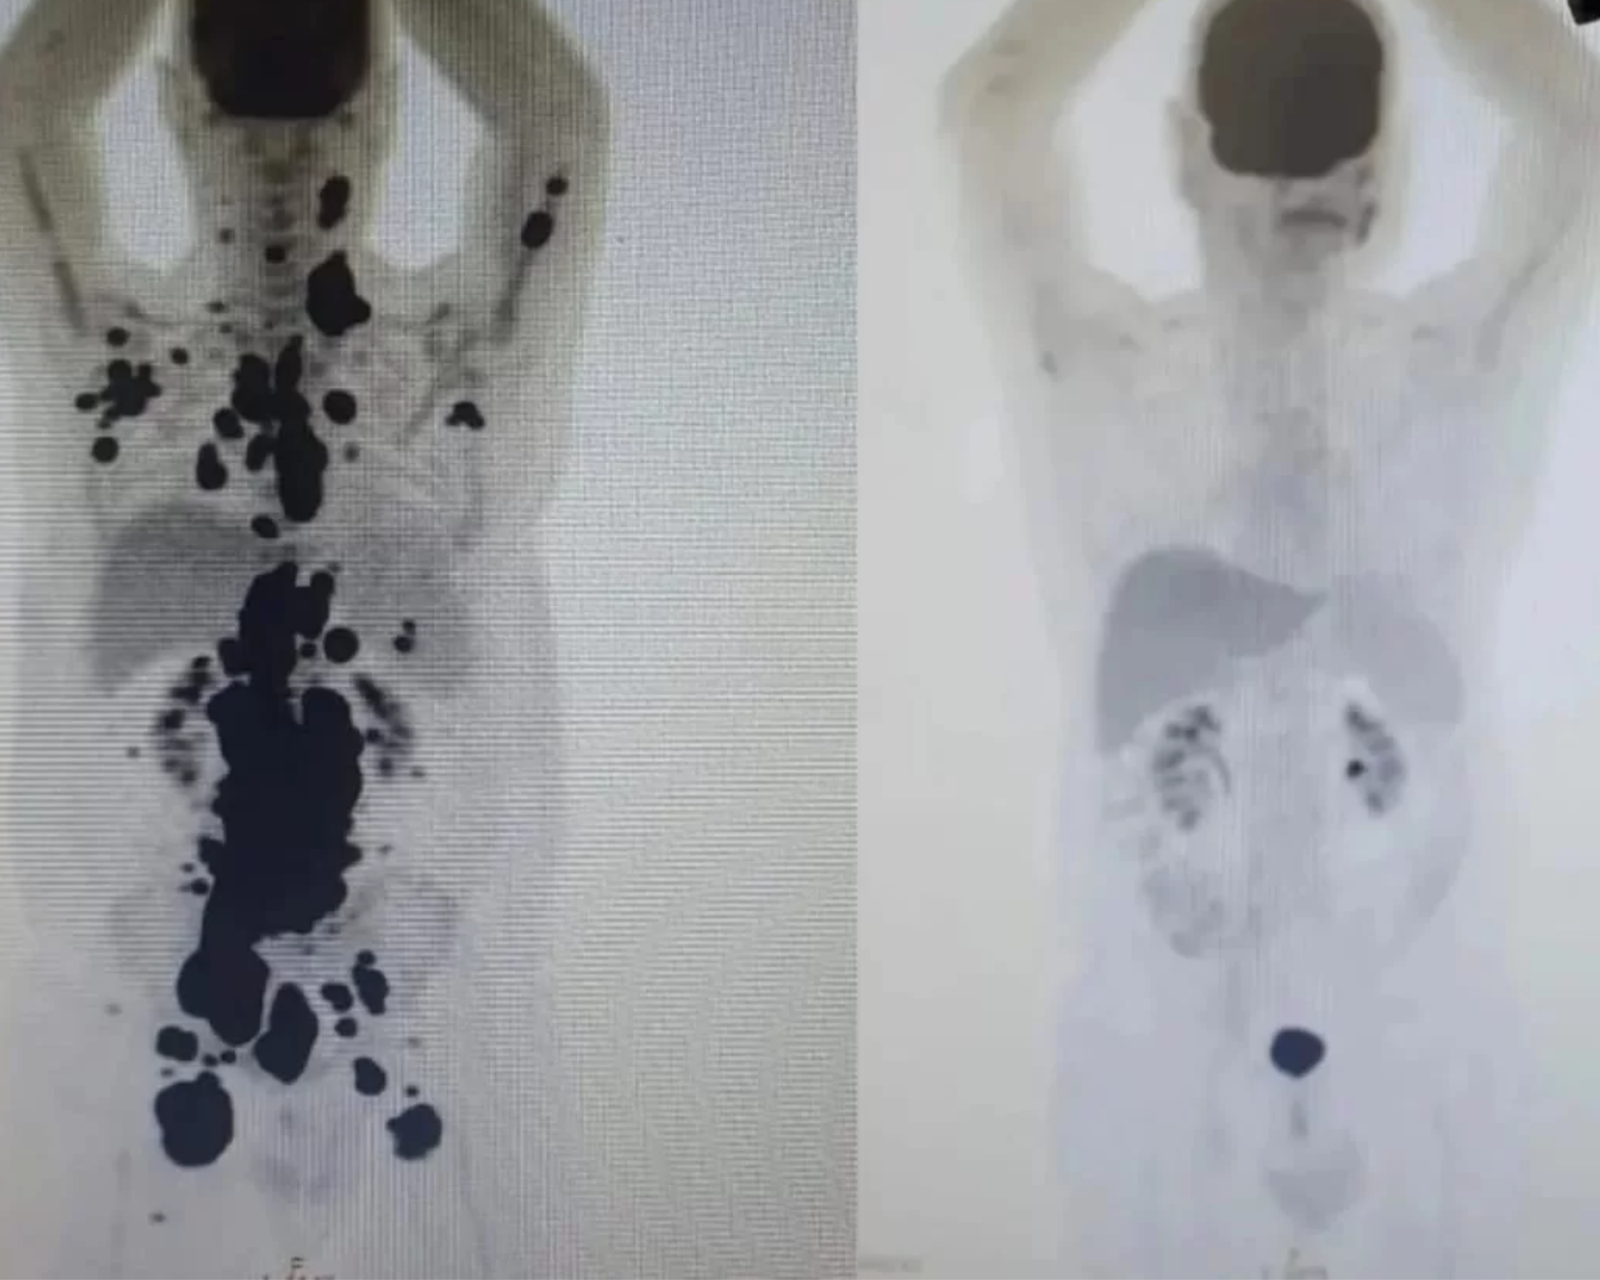

A técnica CAR-T ficou famosa em maio deste ano ao levar o paciente Paulo Peregrino, que tinha um câncer em estágio terminal, à remissão em apenas um mês.